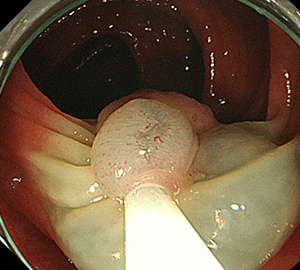

内視鏡的粘膜切除術(EMR)

外来にて切除することの出来ない、比較的大きめの大腸ポリープや平坦な病変などの切除の際に行います。

| 3:ポリープをスネアに通し、周囲の正常粘膜を入れて病変を絞扼 | 4:電気を流してして切除します。 | |

| 5:切除面をクリップで縫合閉鎖し、回収した検体の病理検査に提出します |